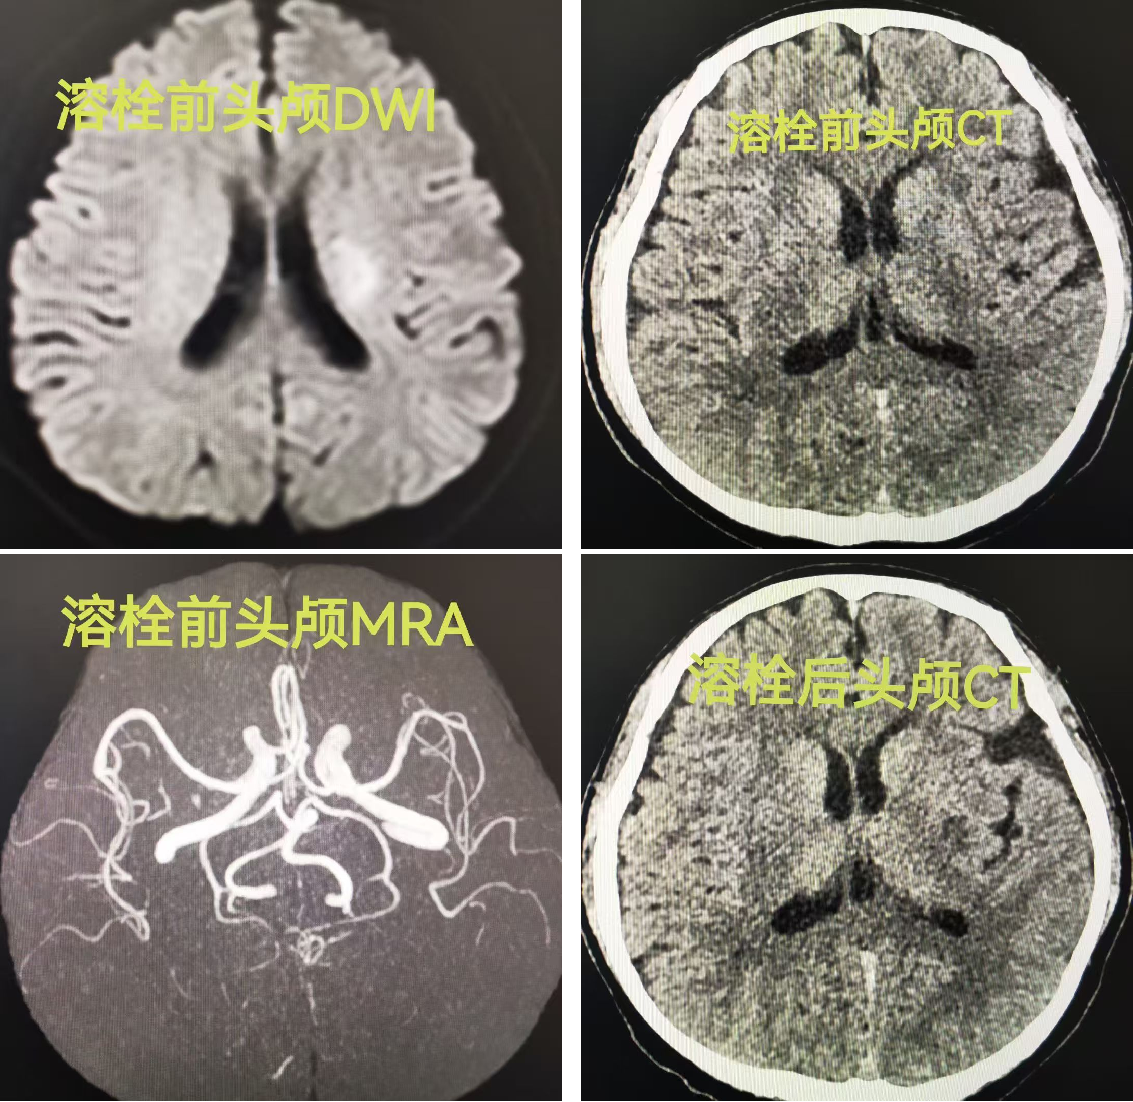

首例患者赵某某,69岁男性,因“突发言语不能、右侧肢体无法活动2小时”来院。入院时,患者完全失语,右侧肢体肌力为0级,无法抬举。急诊卒中医生立即启动急性脑卒中绿色通道,医护协作,抽血、询问病史、快速查体、开具检查同步进行,并全程陪护优先完成影像学检查。头颅CT排除出血,急诊头颅磁共振显检查显示左侧大脑中动脉闭塞、左侧脑室旁及基底节区急性梗死。

卒中中心溶栓专业团队迅速给予静脉溶栓治疗。溶栓结束后,患者言语功能较前改善,右侧肢体能抬举,肌力恢复至4级。次日复查脑磁共振显示,原先闭塞的左侧大脑中动脉已再通。出院时,患者言语流利,四肢肌力恢复正常,行走自如。这场与时间的赛跑,成功避免了患者致残。

第二例是一名40岁青年男性,从事文字秘书工作,无“三高”病史,不吸烟,偶尔少量饮酒,却因突发言语不清、右侧肢体活动障碍40分钟到达医院。入院时言语含糊,右上肢不能抬举,肌力2级,右下肢肌力3级。立即启动急性卒中绿色通道,经急诊CT检查排除出血,进一步急查脑磁共振提示左侧脑室旁急性梗死,MRA未见大血管闭塞。

同样经过溶栓治疗,患者症状明显缓解,次日复查头颅CT示左侧脑室旁梗死灶,没有出血。住院期间,单位领导前来慰问,对我院卒中中心的快速响应与救治效果给予高度肯定。出院时患者已完全恢复正常,重返工作和生活。若非及时溶栓,一旦致残,不仅严重影响生存质量,而且个人前途受阻,也将为家庭带来沉重负担。